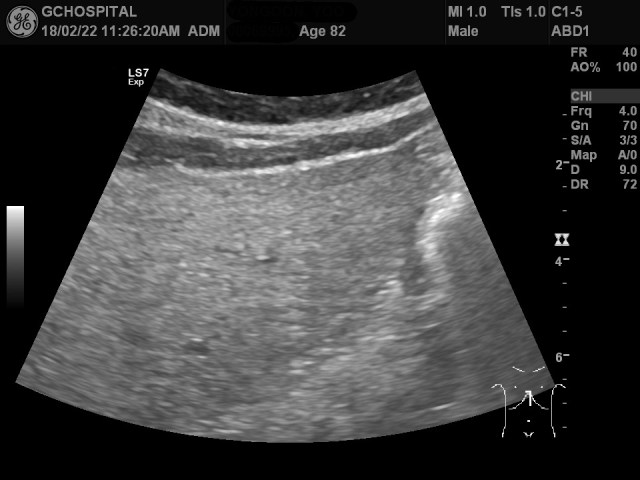

이 환자는 82세 남자환자로서 예전부터 간기능수치가 매우 높았던 만성간질환 환자로 내워해서 초음파영상을 시행하였습니다. 위의 영상처럼 매우 거칠고 고에코의 간실질이 확인되므로 만성간염 내지 간경화초기의 가능성을 생각할 수 있습니다. 간좌엽의 anterior surface가 약간 우둘투둘해보이지만, 4.0MHz의 낮은 frequency로는 liver surface를 정확히 관찰하는게 불가능합니다. 이 환자는 복수나 비장종대, varix같은 간경화에서 동반되는 다른 소견들은 보이지 않았습니다.